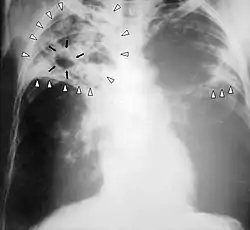

![]() Røntgenbillede af patient med tuberkulose. | |